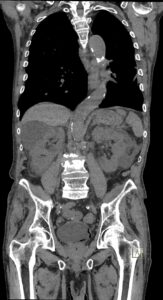

Figurile 4 şi 5: coronal examinare CT abdomen şi pelvis fără substanță de contrast

Discuţie caz nr 131: pacient de 85 de ani cunoscut diabetic este adus la camera de gardă pentru dureri abdominale difuze, efectueaza CT fără substanță de contrast deoarece eGFR este 21 mL/min/1.73 m². Se evidențiază pericardita în cantitate medie, mai multe chiste renale – unul spontan hiperdens, multiple plăci aterotrombotice calcificate la nivelul aortei și ramurilor precum și multiple bule aerice în peretele vezicii urinare și conținut hidro-aeric al vezicii urinare. Ultimele două elemente sugerează diagnosticul de cistita emfizematoasă.